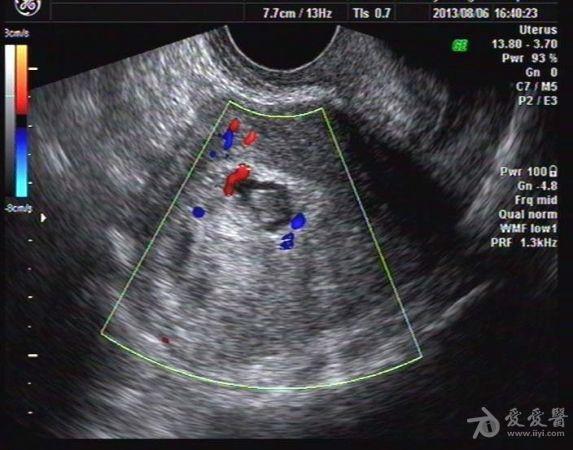

停经47天血HCG大于1万,未稀释 我院B超:子宫大小57x55x61mm,宫内探及一大小约34x27x43mm强回声团块,内回声紊乱,夹杂多个不规则暗区,暗区内未见胚芽及胎心搏动。

该病人子宫增大不明显,无腹痛流血。

手术病检证实:葡萄胎